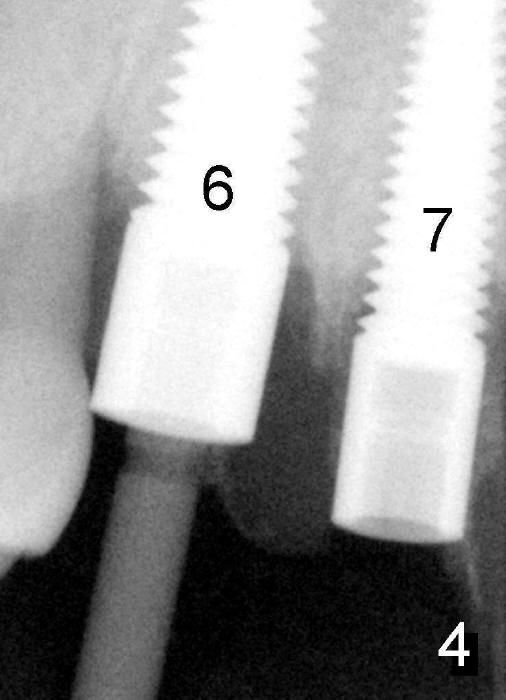

Fig.4 (magnified): Immediately post-implantation: #6: 5x20 mm; #7: 4x20 mm. A straight post guide is inserted as a guide for #7 implant placement. Autogenous bone graft from osteotomy (reamers) is to be placed around the implants.